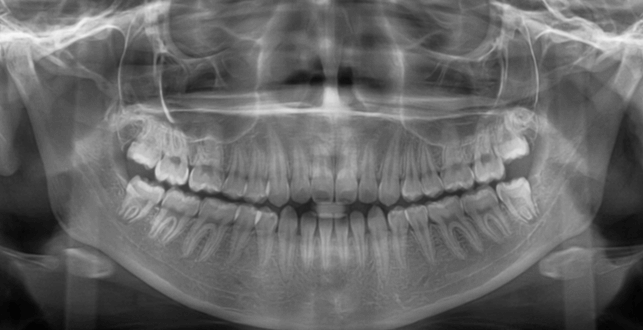

咬み合わせが逆であること(反対咬合)が気になる

| 年齢・性別 | 15歳 女性 |

|---|---|

| 主訴 | 咬み合わせが逆であること(反対咬合)を気にされて来院された女性。見た目や機能面の改善を希望されていました。 |

| 治療期間・回数 | 4年4ヶ月・28回 |

| 費用 | 900,000円 |